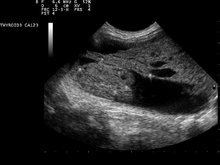

The blood assays may be accompanied by ultrasound imaging of the nodule to determine the position, size and texture, and to assess whether the nodule may be cystic (fluid filled). Also suspicious findings in a nodule are hypoechoic,[9] irregular borders, microcalcifications, or very high levels of blood flow within the nodule. Less suspicious findings in benign nodules include, hyperechoic, comet tail artifacts from colloid, no blood flow in the nodule and a halo, or smooth border.